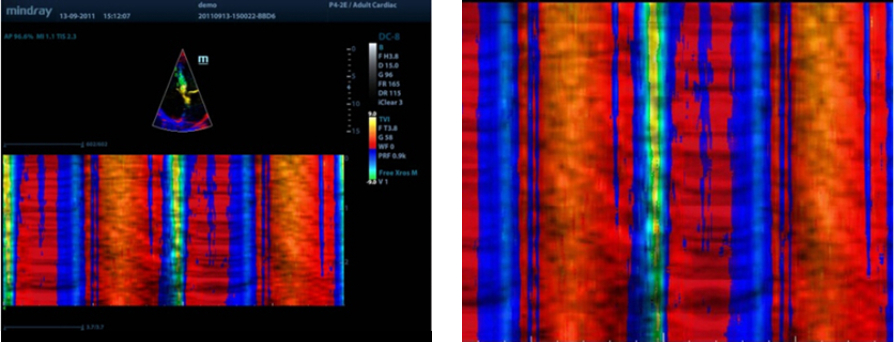

TDI (Doppler tkankowy)

Obrazowanie Tkanek z u?yciem Dopplera - Tissue Doppler Imaging pozwala na ilo?ciow? ocen? miejscowego ruchu i funkcji mi??nia sercowego. Aparat M9 zapewnia kompletny tryb Dopplera tkankowego w celu uzyskania szybszej i bezpo?redniej diagnozy.